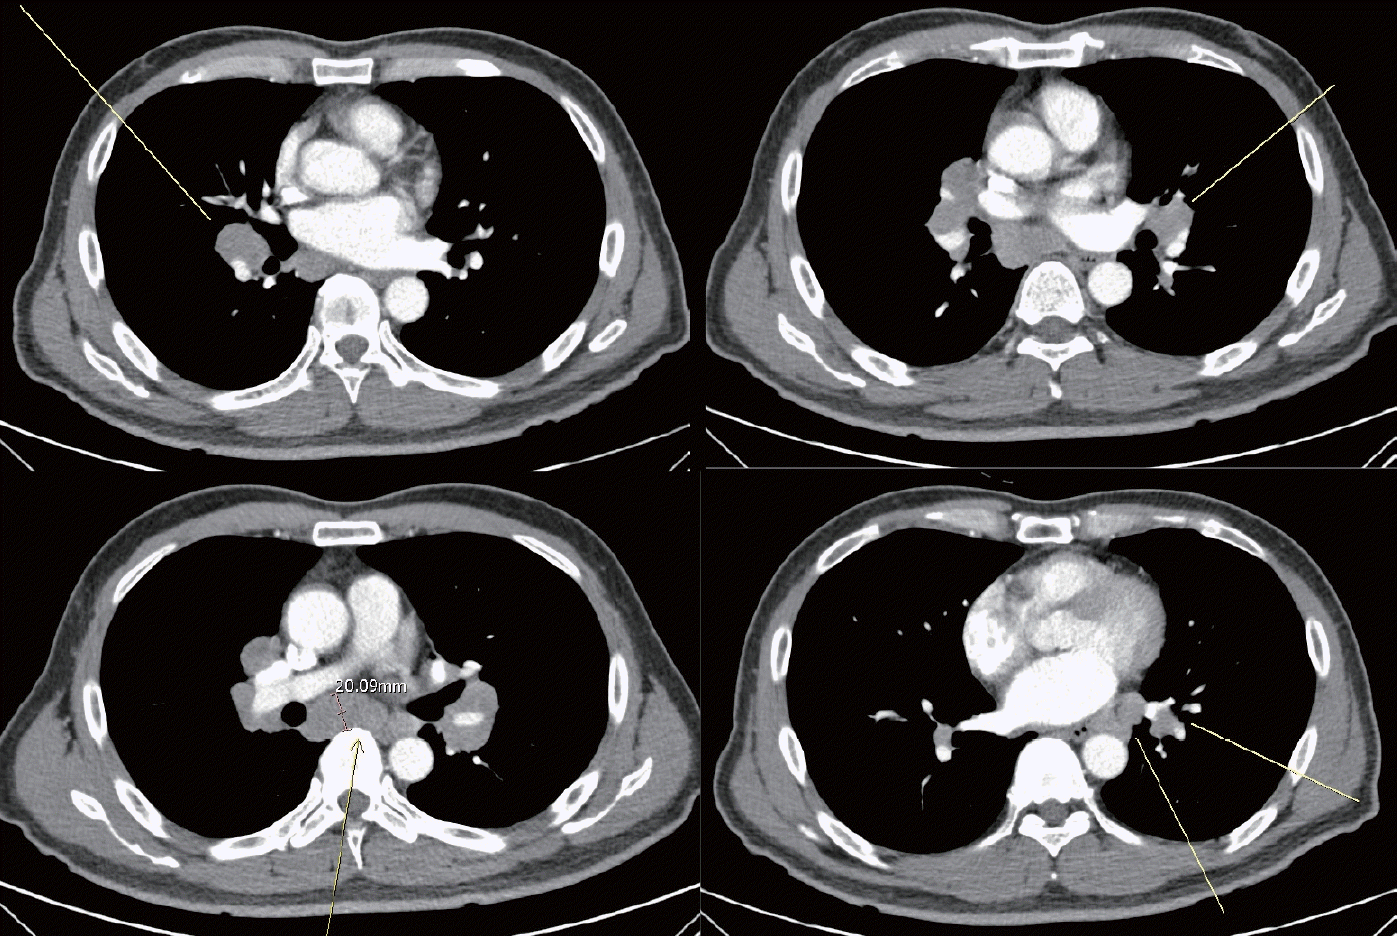

Figure 2.

Contrast-enhanced chest computed tomography. Multiple enlarged lymph nodes in both mediastinal, hilar and interlobar, supraclavicular and paraesophageal areas. These finding most likely sarcoidosis.

환자는 신경계를 포함하여 특별한 과거 병력은 없었고, 결핵, 감염성 질환 및 흡연이나 다른 약물에 노출된 병력도 없었으며, 유전질환의 가족력도 없었다. 이학적 검사상 특이 소견은 없었고 신경학적 검사상 정신상태검사는 정상이었다. 뇌신경검사에서 양측 얼굴의 통증 및 온도 감각이 저하된 소견이 보였고 그외 다른 뇌신경계는 정상이었다. 상지 및 하지의 근력 및 감각 기능은 정상적으로 유지되고 있었으나 양측 손목 이하로 주관적인 저림감을 호소하고 있었다. 팔다리 심부건반사 및 소뇌 기능 검사는 정상이었다. 전기생리학적 검사에서 상하지의 신경전도검사(nerve conduction study, NCS)는 정상이었고, 얼굴신경전도검사(facial NCS)와 신경흥분성검사(nerve excitability test)는 정상이나 눈깜빡반사검사(Blink test)에서 양측 삼차신경병증을 시사하는 소견이 관찰되었다(Table 1). 일반혈액검사에서는 정상이었으나, ACE가 비정상적으로 증가(82 U/L [20-70 U/L])되어 있었다. 자가면역질환과 관련된 항체검사들(antinuclear antibody, anti-Ro/SS-A antibody, anti-La/SS-B antibody, anti-dsDNA, lupus anticoagulant) 및 혈청이나 소변의 면역전기영동검사는 정상이었다. 뇌 자기공명영상은 정상이었으나 뇌척수액검사에서 염증세포가 증가되어 있었고(white blood cell 20/mm3, lymphocyte 100%), 단백질도 증가되어 있었다(94.9 mg/dL). 흉부 X선 촬영에서 양측 폐문과 종격동 림프절 종대가 관찰되었고(Fig. 1), 흉부 전산화단층촬영에서도 폐문, 종격동, 폐엽, 폐상부, 식도부 주위를 비롯한 여러 부위에 림프절 종대가 확인되어 사르코이드증에 합당한 소견이었다(Fig. 2). 사르코이드증의 확진을 위하여 조직검사를 시행하였고, 비치즈화 육아종(non-caseating small granulomas)이 확인되어 사르코이드증으로 확진할 수 있었다(Fig. 3).